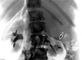

Диагностический пневморетроперитонеум используется главным образом для выявления опухолей надпочечников, а также пороков развития и других патологических изменений почек (рис. 1, 2) в тех случаях, когда не удается провести ультразвуковое исследование (см. Ультразвуковая диагностика), компьютерную томографию и ангиографию. Диагностические возможности пневморетроперитонеума увеличиваются при его сочетании с экскреторной урографией, ретроградной пиелографией, томографией.